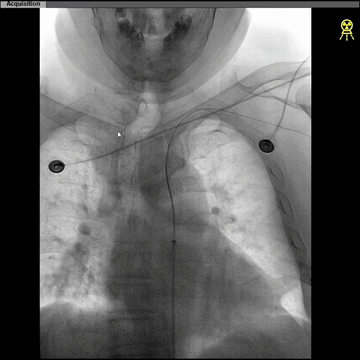

西蒙管于左CCA造影,用硬泥鳅导丝超选入枕动脉,并西蒙管前推上高到枕动脉,加强上支撑,后长鞘顺利过弓,抵达左CCA远端。

建立治疗通路后,保护伞下(NAV6 4-7mm)行左侧ICA起始部狭窄支架植入(wallstent 9*40mm)。